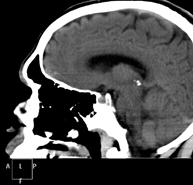

- TC Cráneo

Prueba radiológica que consiste en obtener imágenes del cráneo de alta definición anatómica (tronco cerebral, cerebelo, cerebro, calota craneal, etc.), mediante el empleo de un equipo de TC (Tomografía Computarizada).Indicaciones: traumatismos, cefalea, trastornos de la memoria, pérdida de fuerza súbita en una extremidad o mitad del cuerpo. - TC Cuello

Prueba radiológica que consiste en obtener imágenes del cráneo de alta definición anatómica mediante el empleo de un equipo de TC (Tomografía Computarizada). Indicaciones: cefalea, estudio de tumores, traumatismo craneal. - TC Cuello